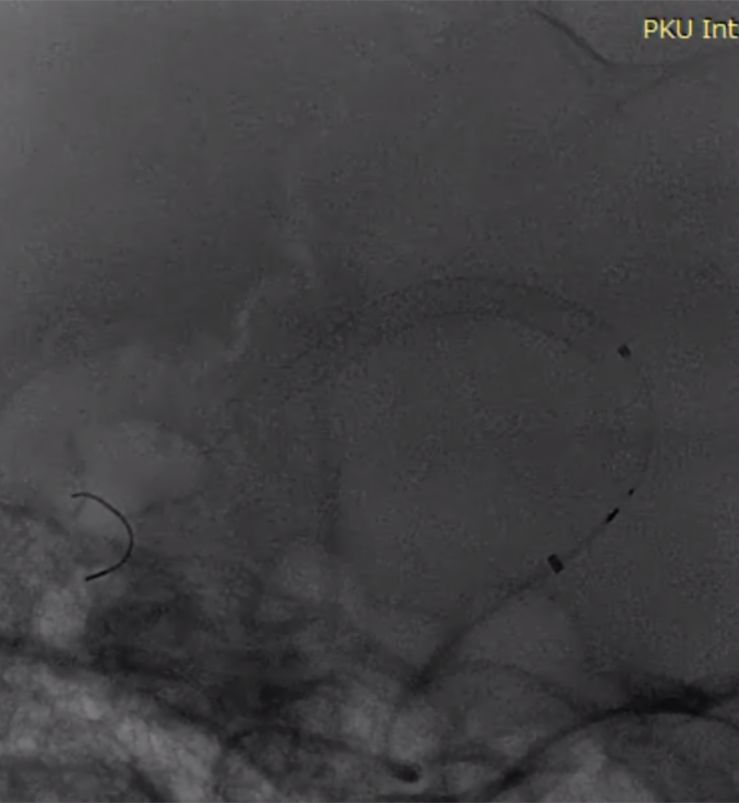

术前造影:

(1)右侧颈内动脉海绵窦段至颈内动脉末端巨大夹层动脉瘤伴血栓形成(图1)。

图1